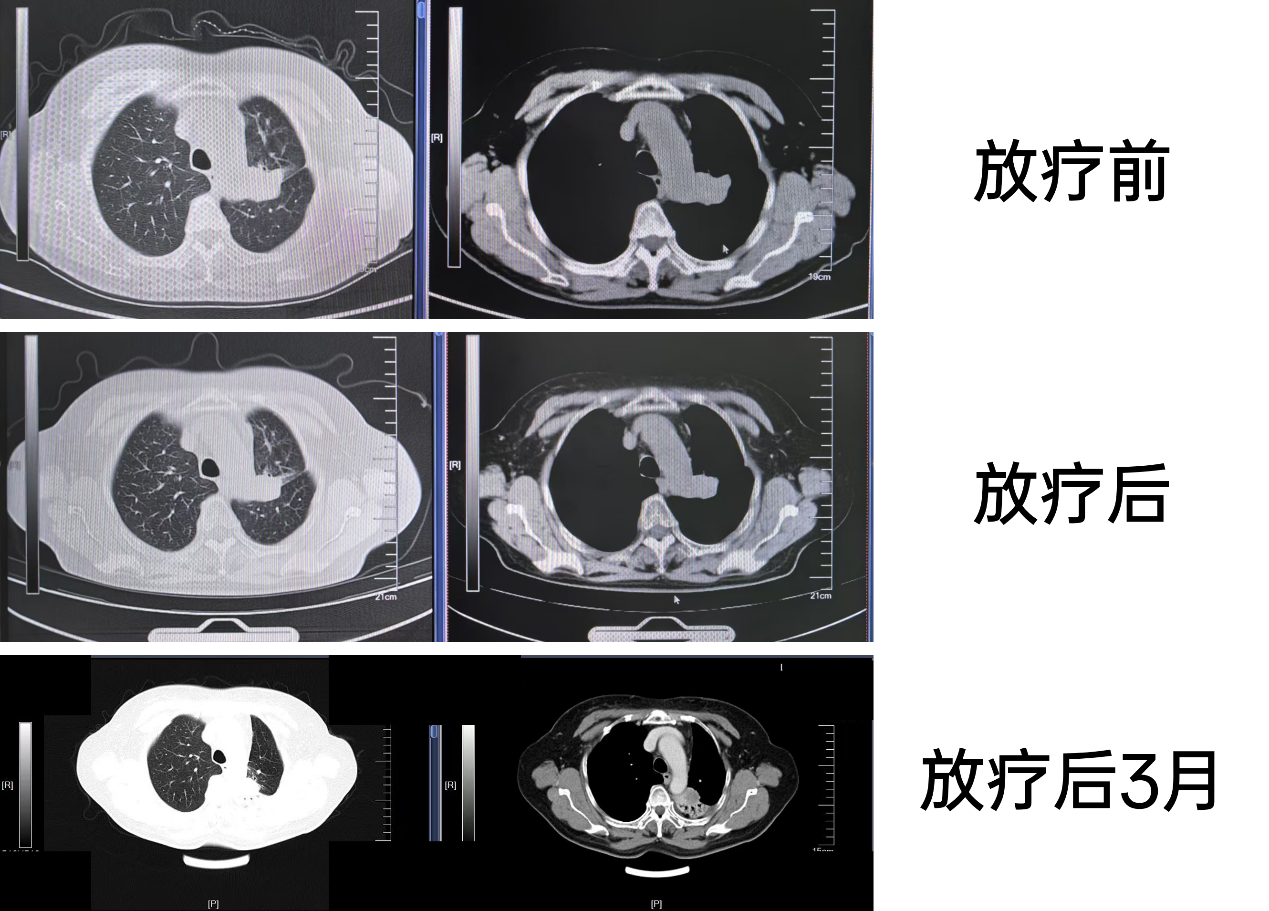

放疗前:2022-11-29, 原诊“肺癌脑转移放疗后半年”复查,与2022-08-16对比:左肺上叶可见软组织肿块影,最大截面约39mm×25mm,形态不规则,相应支气管截断,远端可见阻塞性肺不张,较前略增大。2. 余双肺内可见多发结节影,边缘毛糙,较前变化不著。3. 纵隔可见多发小淋巴结,较前变化不著。4. 双侧胸腔及心包未见积液。5. 甲状腺可见结节及钙化影,较前大致相仿,结合超声。6. 右侧第3肋骨局部密度不均匀,较前变化不著。7. 肝右缘斑点状致密影,较前相仿。8. 胆囊、胰腺、脾脏、双肾及肾上腺未见明显异常密度灶。9. 腹腔、腹膜后未见明显肿大淋巴结影。未见腹腔积液。

放疗后:2023-02-28,原诊“肺癌脑转移治疗后”复查,与2023-01-29比较:左肺上叶可见软组织肿块影,最大截面约29mm×20mm,形态不规则,相应支气管截断,远端可见阻塞性肺不张,较前稍缩小。2. 余双肺内可见多发结节影,边缘毛糙,较前变化不著。3. 纵隔可见多发小淋巴结,较前变化不著。4. 双侧胸腔及心包未见积液。5. 甲状腺可见结节及钙化影,较前大致相仿,结合超声。6. 右侧第3肋骨局部密度不均匀,较前变化不著。7. 肝右缘斑点状钙化灶,较前相仿。

放疗后3个月:2023-05-29,复查上腹部+胸部CT:原诊“左肺癌脑转移治疗后复查,与2023-04-04比较:1. 左肺上叶可见软组织肿块影,最大截面约32mm×23mm,形态不规则,轻度强化,相应支气管截断,周围可见肺不张,整体范围较前增大。2. 左肺片絮影,范围缩小,大部分已不明确。余双肺内可见多发结节影,边缘毛糙,较前变化不著。3. 纵隔可见多发小淋巴结,较前变化不著。4. 双侧胸腔及心包未见积液。5. 甲状腺可见结节及钙化影,较前大致相仿,结合超声。6. 双侧多条肋骨局部密度增高,考虑为陈旧性骨折,结合临床。7. 肝右缘斑点状致密影,较前相仿。8、胆囊、胰腺、脾脏、双肾及肾上腺未见明显异常密度灶,较前相仿。9. 腹腔、腹膜后未见明显肿大淋巴结影。10. 未见腹腔积液。